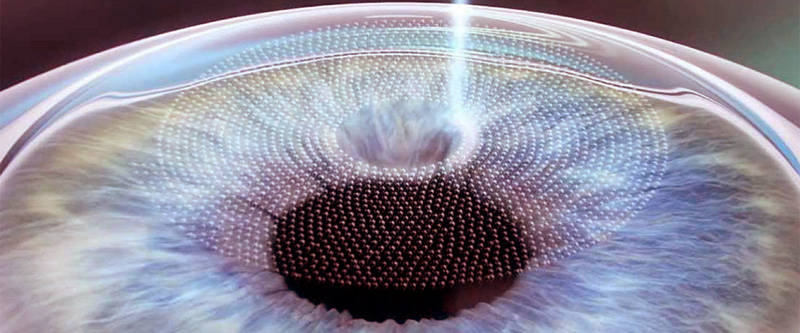

Wavefront Technique

What is Wavefront Technique?

Wavefront Technology is also called Customized treatment – eagle eye technique.

The purpose of the standard Lasik technique is to eliminate the diopter value.

However, the purpose is to enhance the quality and level of vision as well as to reduce the night vision problems. Particularly, more qualified and better vision is ensured that can not be provided with standard therapy for the patients with corneal irregularity who are not able to see well depending on amblyopia.

Wavefront technology has been used to take more clear pictures space with telescope in the area of astronomy for years.

The waves of light enter parallelly in our eyes, but as they go through pane, lens and cornea the light here returns back wavily resulting in deviations (aberrations).

Three dimensional image is transferred to the laser via a disk. The maps which are recorded with aberometry are personal and they are exactly footprints.

How is Wavefront Applied?

All layers of the eye are measured using a device called Wavefront Analyzer (Aberometry) and the deviations and irregularities here are mapped as per each eye. This map is then transferred to the laser device and special treatment is planned for each eye.

Since Wavefront maps are different for each individual footprints, the treatment is considered customized for the patients.